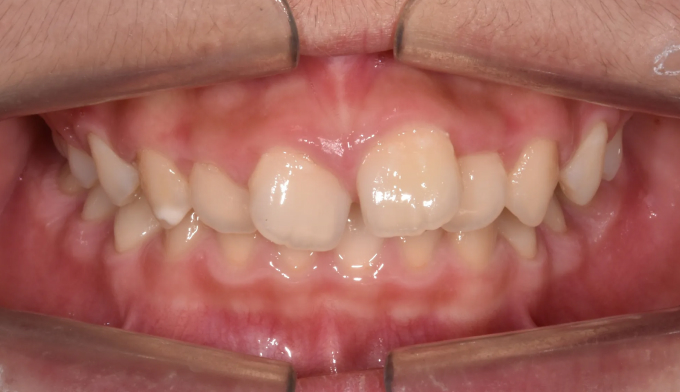

앞니공간,

주걱턱

20대

2025.02.11